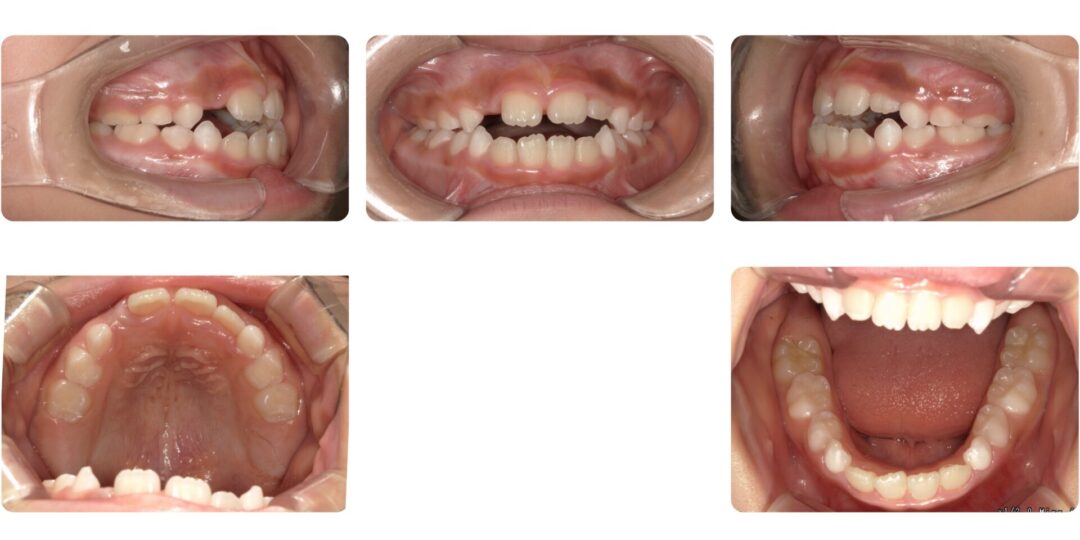

反対咬合を伴う骨格性開咬|初診時7歳

口呼吸が多く口が開いている、物を噛む回数が少ない

第一期治療 プレオルソによる歯列矯正

1年5ヶ月